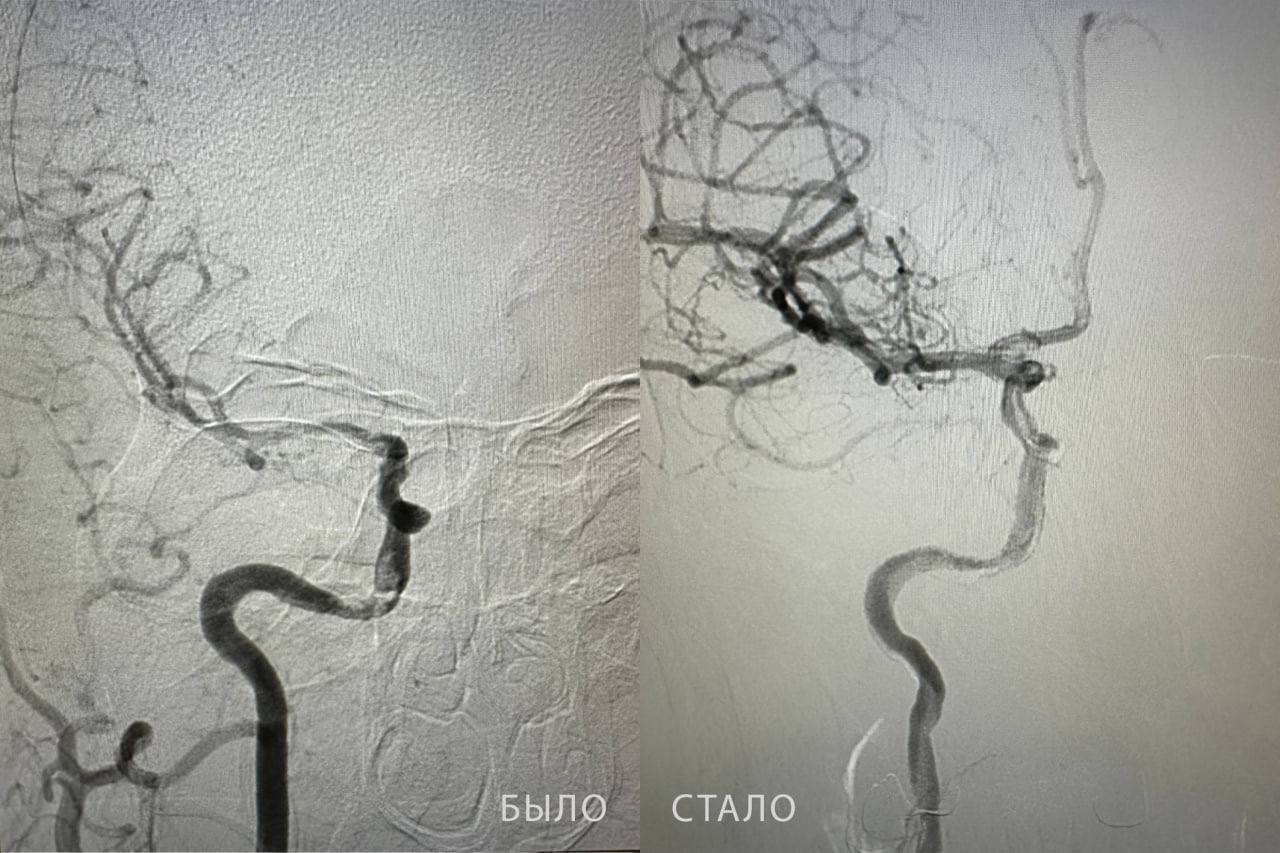

Специалисты в ходе исследования кровеносных сосудов обнаружили тромб в правой внутренней сонной артерии. Врачи провели сложную операцию и извлекли из сосуда тромб длиной почти 2 сантиметра.

У пациента полностью восстановились речь, симметрия лица и двигательная активность.